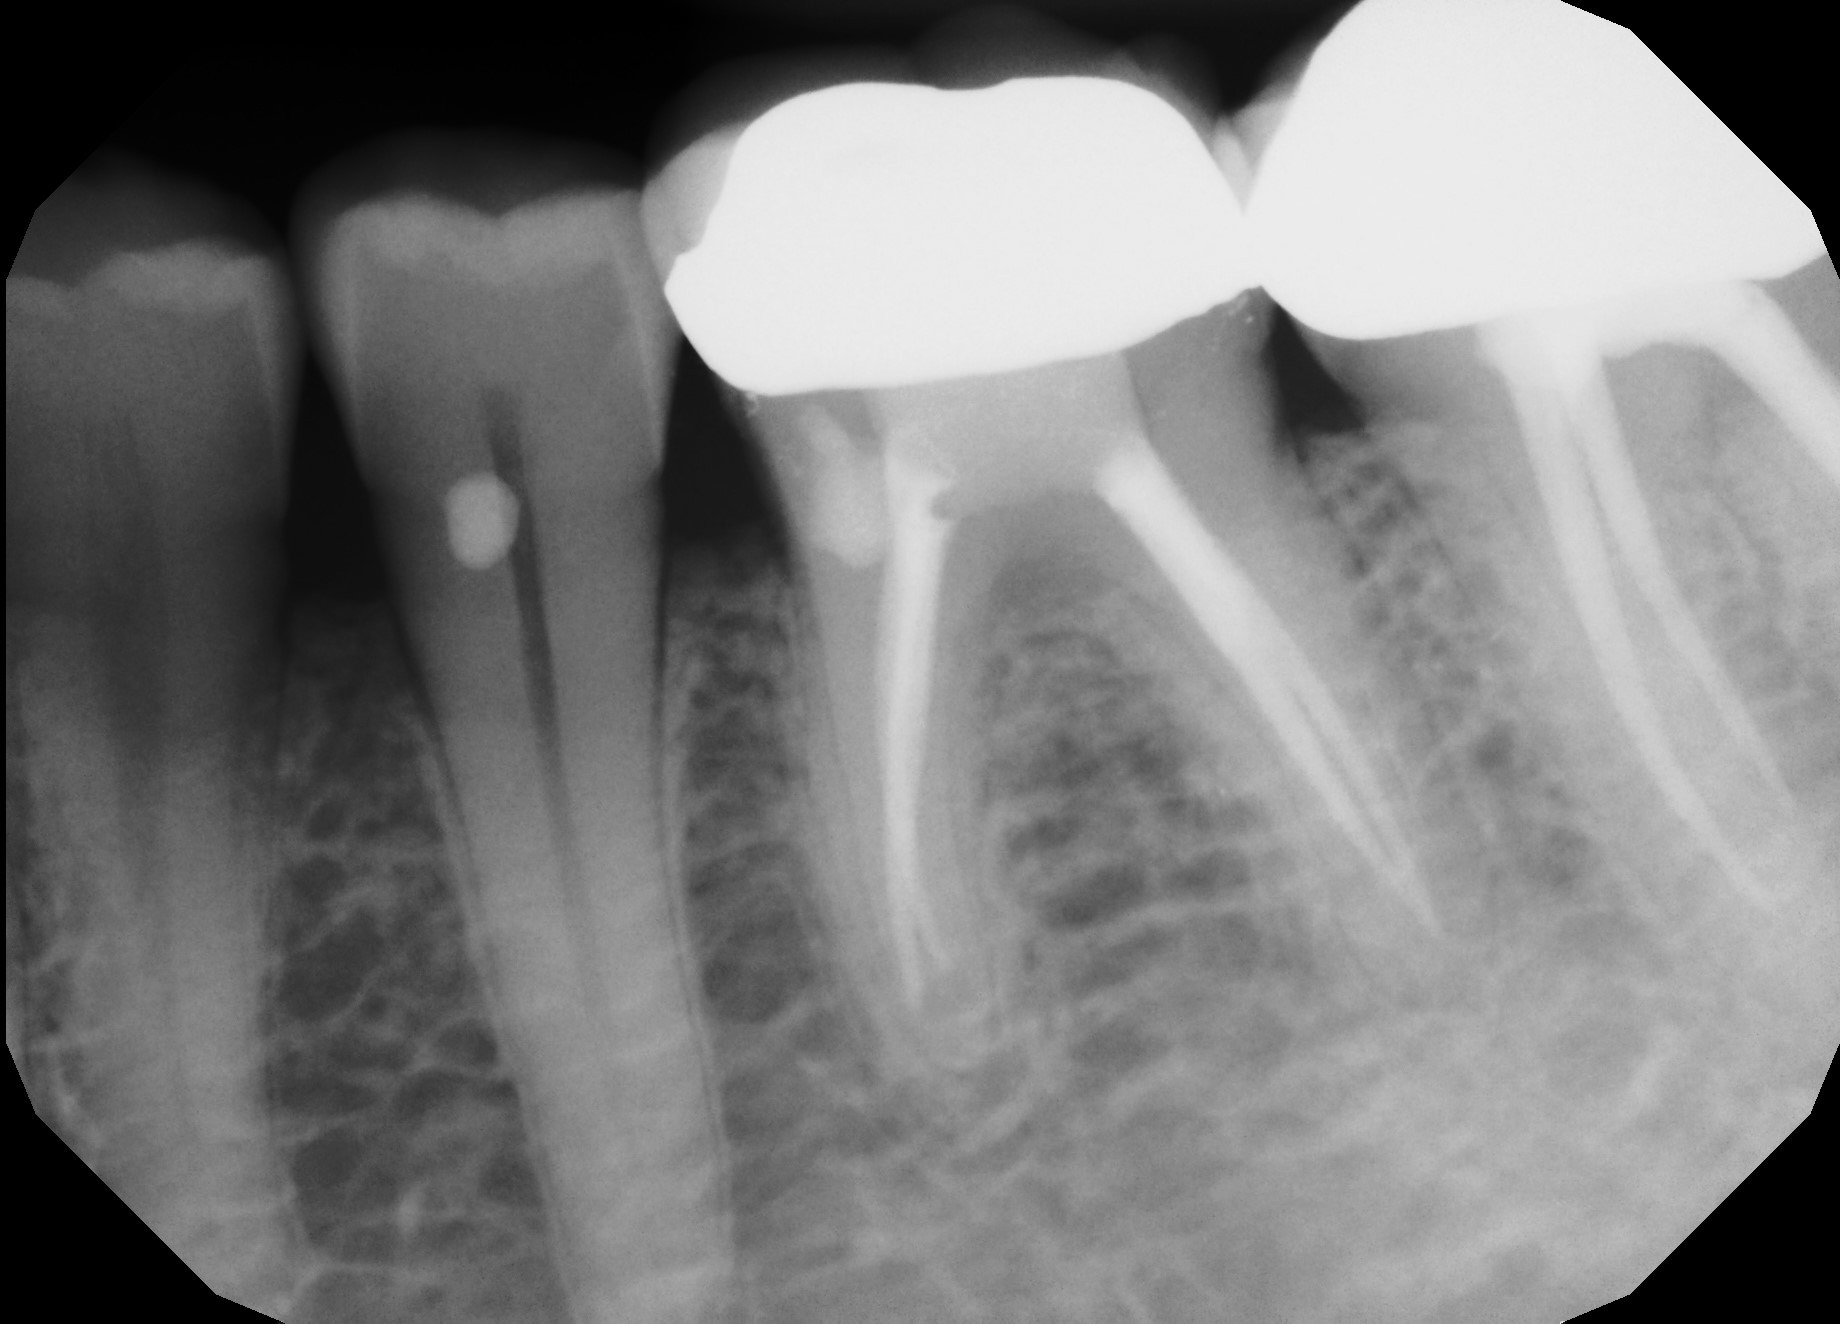

Richard Mounce and Brett Gilbert explore new technologies, hybrid strategies and proven solutions in canal enlargement.